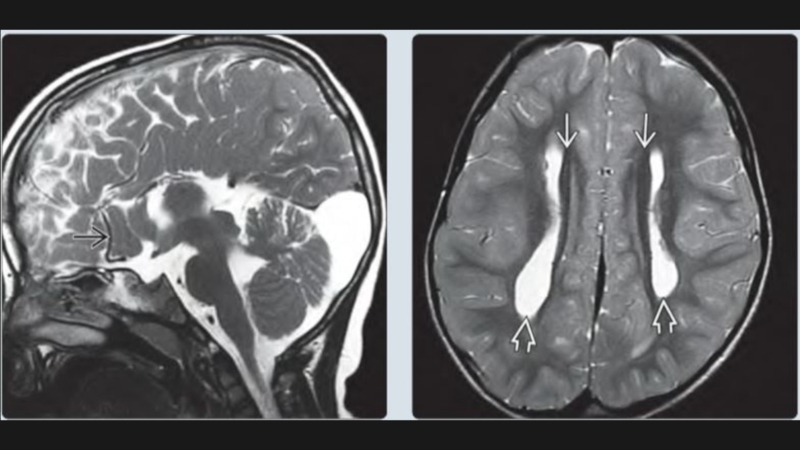

Слайд 28Дисгенезии мозолистого тела

Визуализация:

Отсутствие мозолистого тела на саггитальных, корональных

срезах

На месте отсутствующего мозолистого тела тракты вместо перекреста образуют пучки

Пробста(DTI)

Боковые желудочки разделены и параллельны

Преддверие/затылочный рог бокового желудочка часто расширены

(кольпоцефалия)

Спектр врожденных структурных аномалий МТ

-тотальная агенезия

-частичная агенезия

-гипоплазия

-гиперплазия

Дисгенезии мозолистого тела Визуализация: Отсутствие мозолистого тела на саггитальных, корональных срезахНа месте отсутствующего мозолистого тела тракты вместо